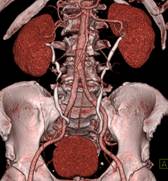

※肝脏、胰腺、肾脏CT-DSA 及灌注功能一站式检查